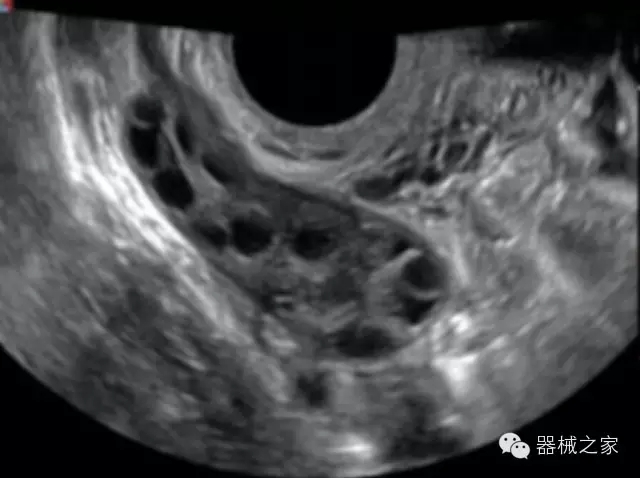

臨床圖片賞析

產(chǎn)品特點(diǎn)

·獨(dú)有的RF平臺提高微小細(xì)節(jié)顯示、圖像對比度和邊界清晰度;

·特有的XCEN探頭,超寬的帶寬,表現(xiàn)更高分辨率和對比度;

·單晶純凈波探頭提供更佳的穿透力和彩色敏感度;

·完整的3D/4D臨床應(yīng)用,STIC, MCUT 和Auto NT等滿足產(chǎn)科所有應(yīng)用;

·更高的HQ羊膜腔鏡成像技術(shù)精細(xì)觀察每一個暗區(qū)細(xì)節(jié);